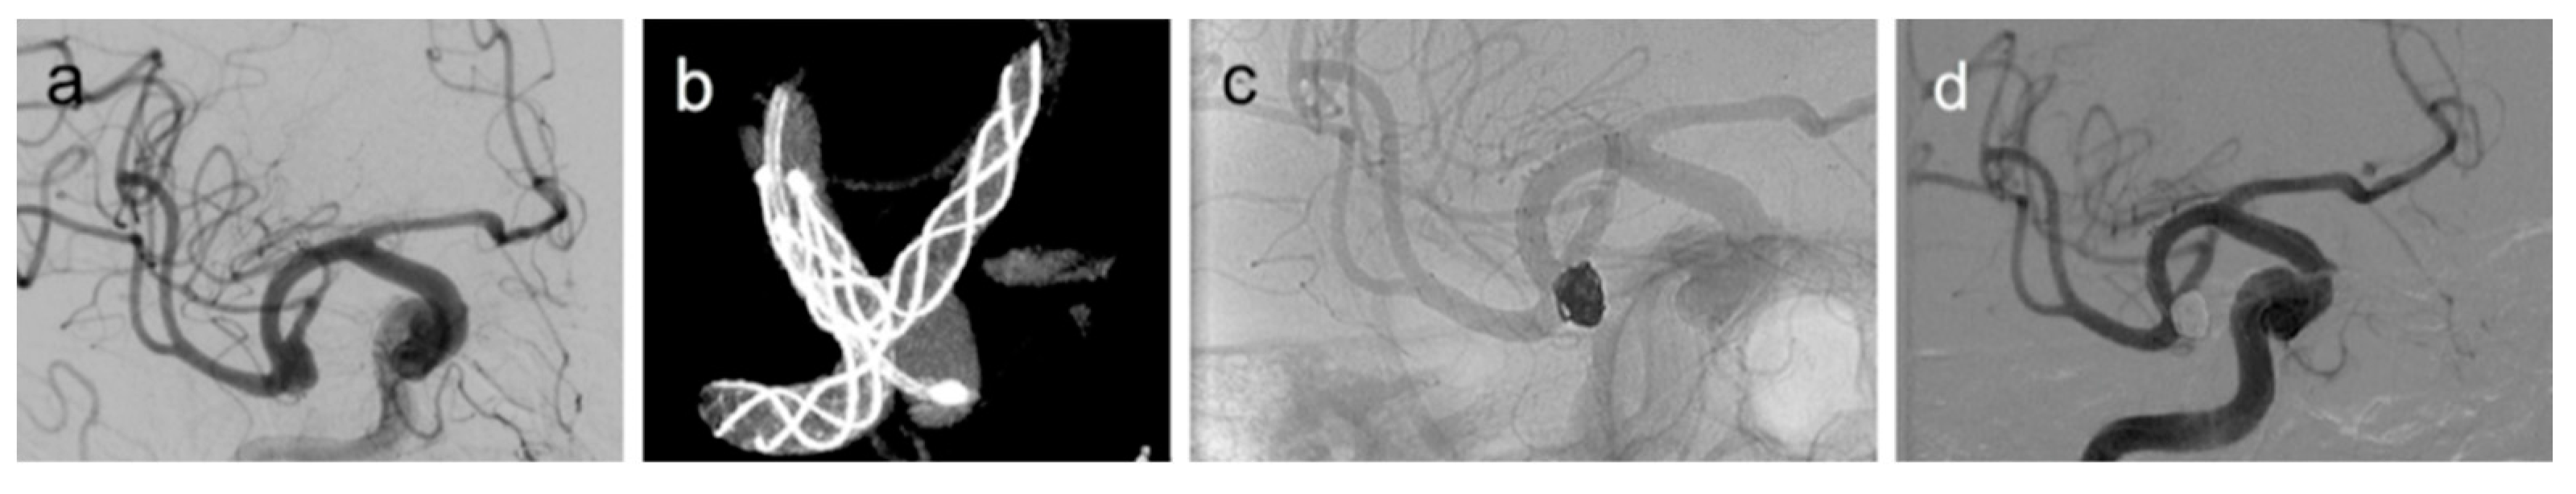

- Feng, Z.; Li, Q.; Zhao, R.; Zhang, P.; Chen, L.; Xu, Y.; Hong, B.; Zhao, W.; Liu, J.; Huang, Q. Endovascular Treatment of Middle Cerebral Artery Aneurysm with the LVIS Junior Stent. J. Stroke Cerebrovasc. Dis. 2015, 24, 1357–1362. [Google Scholar] [CrossRef] [PubMed]